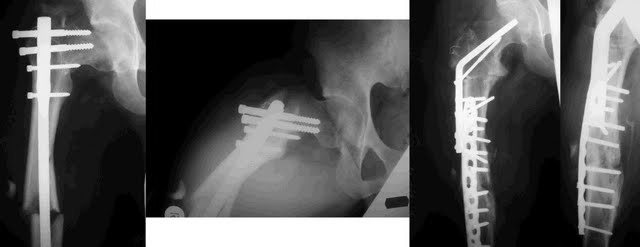

[Ortho] неправильно-срастающийся черезвертельный перелом после Gamma-long

Вальгизирующая остеотомия, фиксация клинковой 130 градусной в один или два изгиба  в зависимости от СORA по Paley. Пример- пациент тоже из Киева, у нас в Киеве, к сожалению,  эпидемия постравматических варусных деформаций.